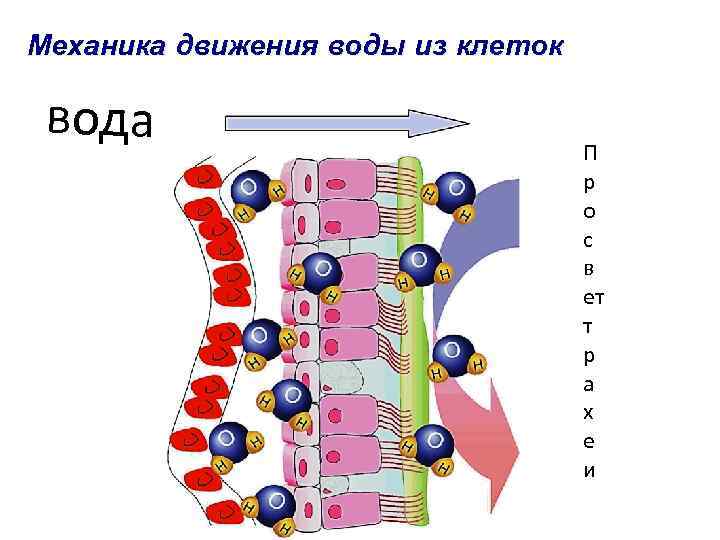

Механика движения воды из клеток вода П р о с в ет т р а х е и

Механика движения воды из клеток вода П р о с в ет т р а х е и

Оптимальное увлажнение Достаточная продукция слизи Хороший транспорт Экономит энергию и воду Защитная функция

Оптимальное увлажнение Достаточная продукция слизи Хороший транспорт Экономит энергию и воду Защитная функция

Нормальное состояние слизистого бронхиального секрета возможно только при 100% относительной влажности воздуха

Нормальное состояние слизистого бронхиального секрета возможно только при 100% относительной влажности воздуха